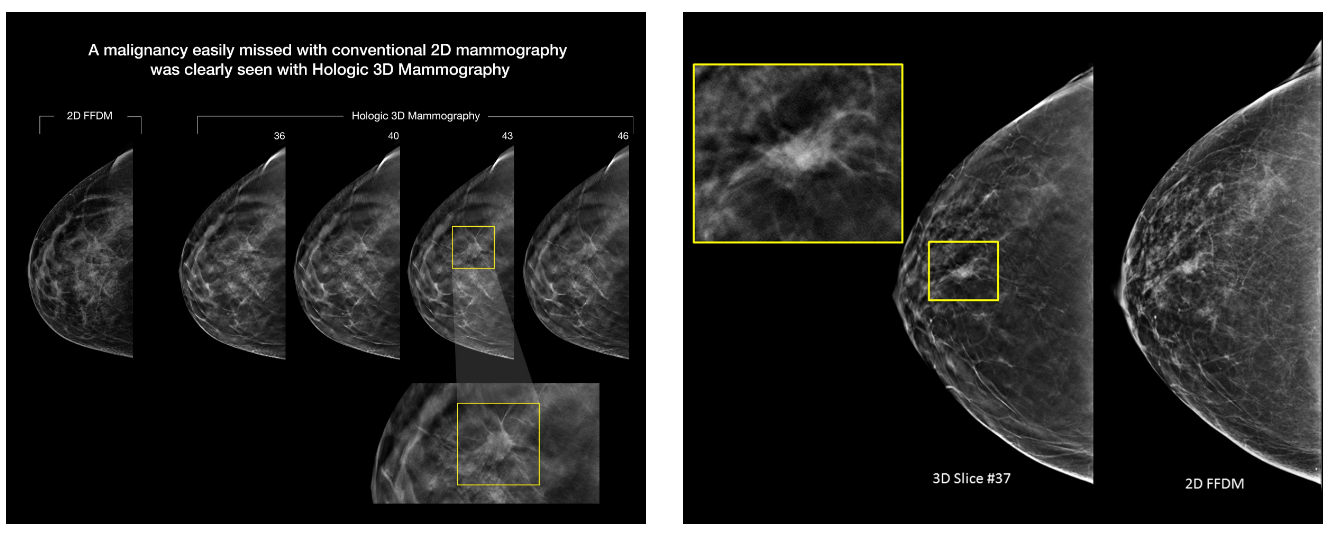

این دستگاه، که از دقیقترین و بهروزترین فناوریهای تصویربرداری پستان در جهان محسوب میشود، قادر است با وضوحی بسیار بالا و از زوایای مختلف، ضایعات احتمالی پستان را در مراحل اولیه شناسایی کند. برخلاف ماموگرافیهای دوبعدی ، در تکنولوژی توموسنتز سهبعدی، بافتهای رویهمافتاده از یکدیگر تفکیک شده و پزشک میتواند با دقتی بینظیر، تفاوت بین بافتهای سالم و تودههای مشکوک را تشخیص دهد.

توضیحات تصاویر: در تصویر بالا مشاهده میشود که ضایعهی بدخیم پستان، در ماموگرافی دوبعدی (2D FFDM) بهراحتی پنهان مانده، اما در برشهای متوالی ماموگرافی سهبعدی Hologic (3D Tomosynthesis) بهوضوح قابل مشاهده است. این فناوری با حذف همپوشانی بافتها، قدرت تشخیص ضایعات اولیه را تا ۴۰٪ افزایش میدهد.